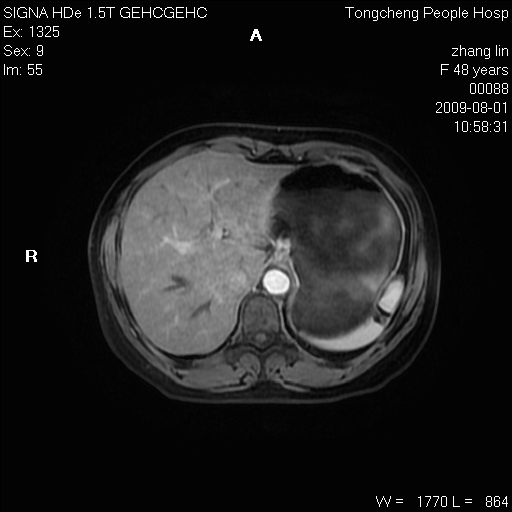

女,48岁。健康体检,彩超发现右肾占位性病变。平素健康。

临床诊断:右肾占位性病变,性质待定(囊肿?肿瘤?)。

上中腹部mr平扫+增强扫描,图像如下:

右肾上极见一类圆形病灶,t1wi呈等信号t2wi呈等高混杂信号,三期增强无强化,边界清---考虑囊肿出血。

肝囊肿

慢性胆囊炎